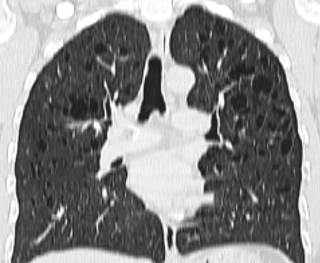

Figura 2: Tomografía computarizada de alta resolución (TACAR), reconstrucción coronal. Mismos hallazgos que la Figura anterior donde se puede objetivar con claridad la predominancia de la afectación pulmonar en campo superior, muy típico de la histiocitosis pulmonar.